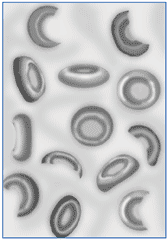

The epidemic EHEC outbreak in Germany, beginning with hemorrhagic diarrhea and abdominal cramps – is very dangerous: The bacterium E. coli O157:H7 causes in combination with Shiga toxins the “hemolytic uremic syndrome” (HUS), in which the red blood cells are destroyed. At first the kidneys fail, then, much more dangerous, the brain is under attack. Therapy: maybe “Eculizumab” (Soliris), produced by Alexion, USA